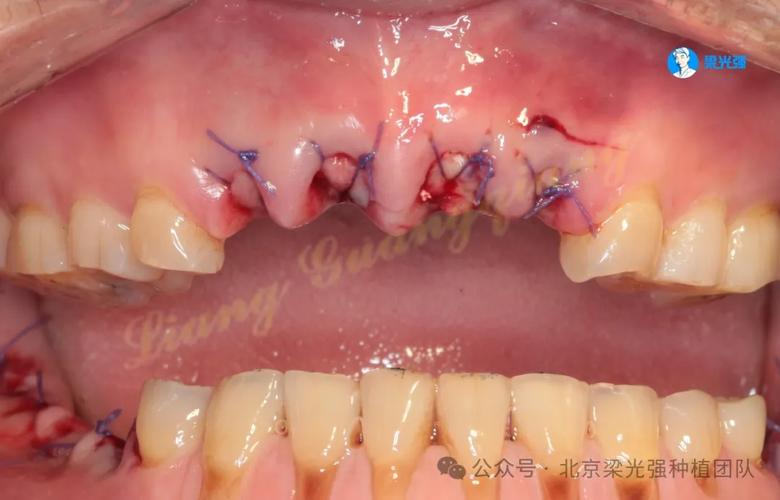

- 骨增量处理:若骨量不足导致失败,可在取出种植体同期或延期进行植骨术(如自体骨移植、骨粉填充),使用骨引导再生膜(GBR技术)引导骨再生,待3-6个月骨愈合充分后,再行二次种植。